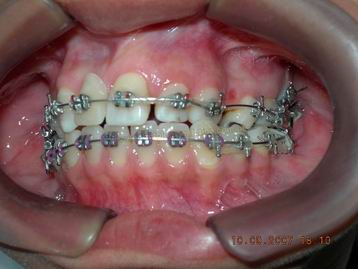

FASE INICIAL DO TRATAMENTO ORTODÕNTICO COM FIO RETANGULAR TERMOATIVÁVEL

|